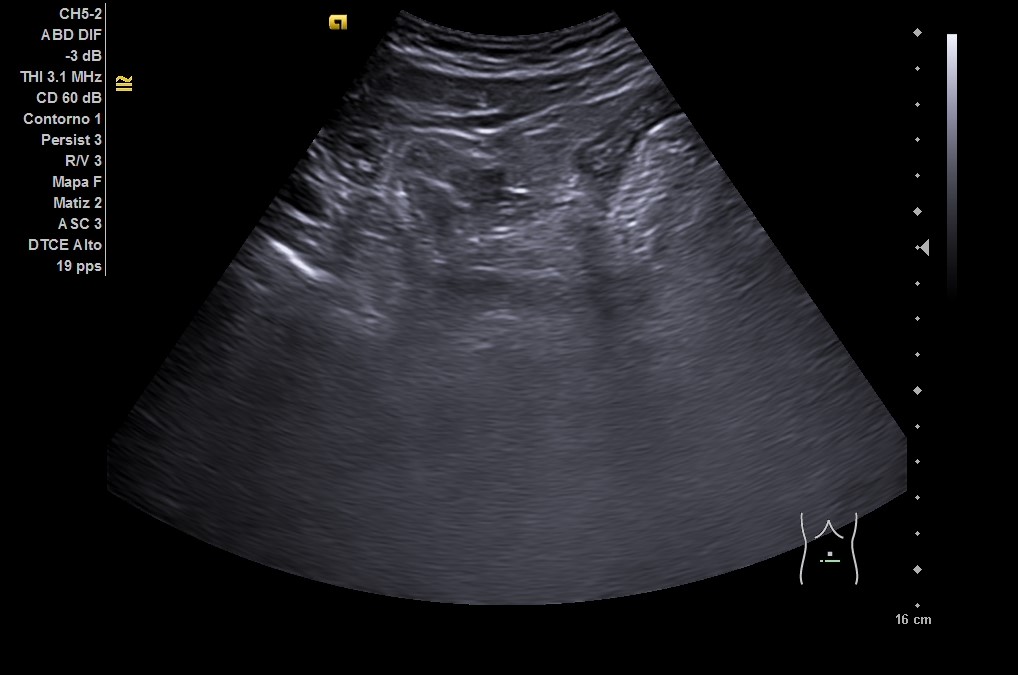

En ecografía clínica: hígado homogéneo sin lesiones, vesícula biliar sin litiasis. Riñones de forma, tamaño y ecoestructura normales. Arteria aorta sin dilataciones. Vejiga levemente repleccionada, ausencia de líquido libre en fondo de Douglas. Asa de sigma con posible edema de pared. Ante la clínica y los hallazgos ecográficos, se remite a urgencias del hospital de referencia.

• En urgencias, de inicio se realiza radiografía abdominal sin datos de obstrucción intestinal. Ante persistencia de dolor intenso, leucocitosis y aumento de PCR en analítica, se repite la ecografía (utilizando también sonda lineal) con hallazgo de diverticulitis aguda sigmoidea con datos de peritonitis regional pélvica, y posteriormente se realiza un TC abdominal con conclusión de diverticulitis aguda con pequeños abscesos murales, perforación de un divertículo y peritonitis pélvica.